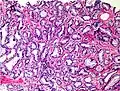

-

Gleason score 6 (3+3) -

Cribriform pattern: Gleason grade 4 -

Gleason score 7 (3+4) with minor component of cribriform glands -

Gleason score 8 (4+4) with glomeruloid glands -

Gleason score 8 (4+4) with irregular cribriform glands -

Gleason score 8 (4+4) with fused glands with cytoplasmic vacuoles -

Gleason score 8 (4+4) with poorly-formed glands -

Gleason score 9 (4+5) with cribriform glands, some with necrosis -

Gleason score 10 (5+5) with cords of cells -

Gleason score 10 (5+5) with individual cells -

Gleason score 10 (5+5) with solid sheets of cells